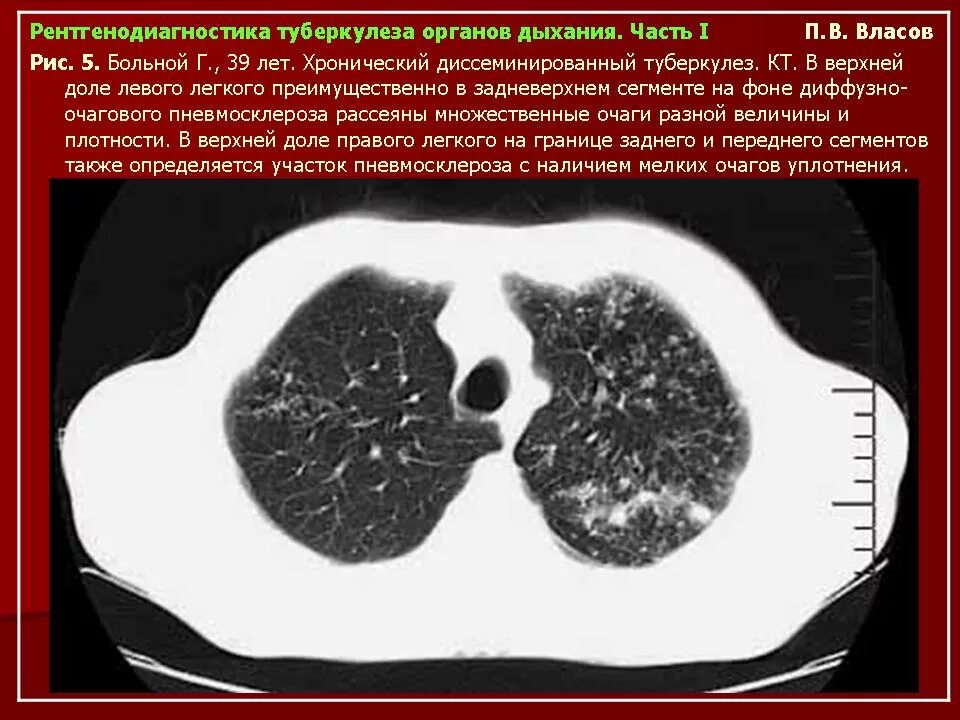

Кт ошибочно